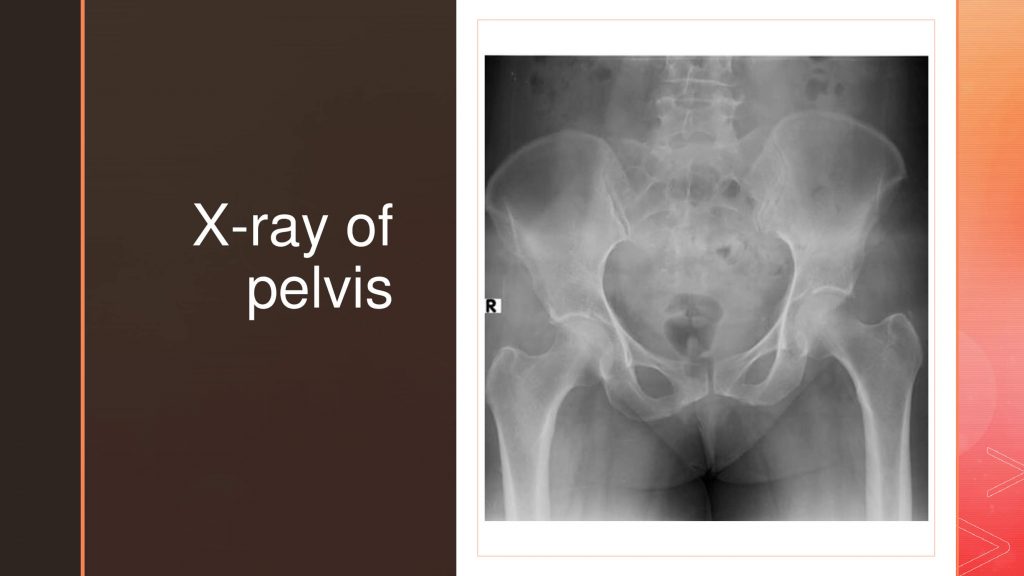

55 years, female presented with back pain of inflammatory nature. She had both knee pain from the age of 40, with episodes of swelling, and inflammatory parameters being significantly elevated. The BMD indicated a significantly low score and no pathological fracture to date, The serum vitamin D levels were also normal. Radiological images of knee joints show normal knee joints, pelvis shows bilateral normal sacroiliac joints.

The present case fulfills the ASAS classification criteria2 (figure 1 & 2) required for axial spondyloarthritis other than age and radiographic features. However, the possibility of spondyloarthropathy is relatively low for these female patients aged above 55 years. Radiographs of the knee and pelvis, and even that of the spine, do not suggest significant degenerative changes. Under the circumstances, one must consider the possibility of Infection including pelvic infection as well the malignancy like Multiple myeloma, as the inflammatory parameters are elevated. Evaluation of electrophoresis suggested an inflammatory pattern. Gynecological evaluation for pelvic infections and malignancy was found to be negative. The patient was HLA B 27 positive and anti-CCP negative.

Spondyloarthropathy, though common in the younger age group, is adequately described in the literature. The clinical spectrum may vary, and age can be up to 70 years.3 The present patient fulfilled the ASAS criteria, in addition to being HLA B 27 positive and having elevated inflammatory parameters whereas the radiographic imaging indicates no damage to the knees and pelvic joints. Axial arthritis with no damage to the sacroiliac joints is considered non-radiographic axial spondyloarthropathy4.